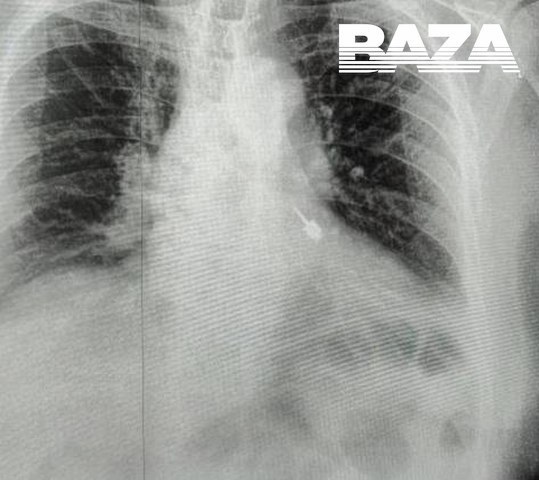

Во время приёма инструмент оказался в дыхательных путях мужчины. Он сразу почувствовал боль и отправился в больницу. Рентген показал, что бур находится в левом бронхе. Медики приняли решение экстренно прооперировать пациента, так как любое промедление могло привести к тяжёлым осложнениям, вплоть до летального исхода.

Врачам Мытищинской больницы предстояло выполнить ювелирную работу — при извлечении острая часть бура могла повредить стенки бронха и спровоцировать кровотечение. Поэтому действовать приходилось предельно точно. С помощью эндоскопа стоматологический инструмент зафиксировали и плавно извлекли, не травмировав ткани.